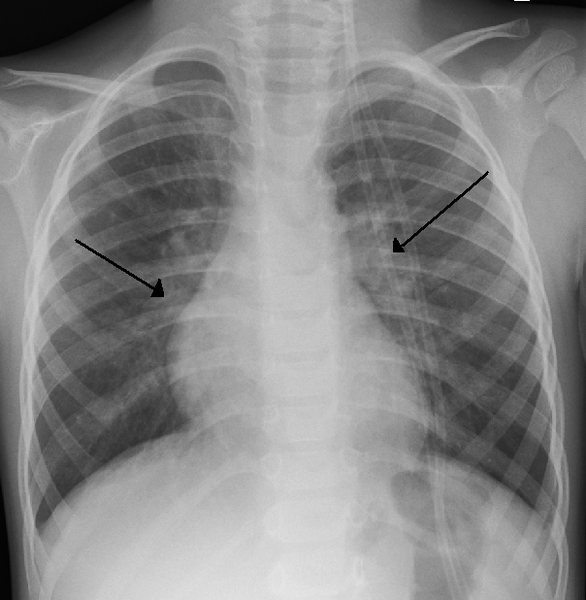

Diagnosis of the condition is made by physical exam, pulse oximetry (which measures oxygen levels), and chest x-rays. In severe cases, chest X-rays may show changes in the lungs such a hyperinflation. A test for the RSV antigen can be helpful. Bronchiolitis is caused by viruses including parainfluenza virus type 3, respiratory syncytial virus (RSV), and rhinovirus.

- Bronchitis is not normally evident on a chest X-ray but bronchiolitis can sometimes be seen on a chest X-ray since it can causes changes in the lungs.